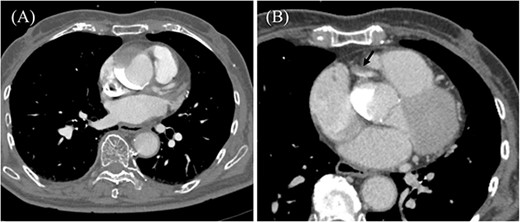

An 85-year-old woman with a history of hypertension and cerebral infarction presented to the emergency department of another hospital with the complaint of temporary loss of consciousness (LOC). Dehydration was suspected to be the cause of LOC; however, CAG was performed to confirm the reason for the mild elevation in creatine kinase and D-dimer levels. While the left coronary system was intact (Fig. 1A), the coronary dissection spread retrogradely from the right sinus of Valsalva to the ascending aorta after injecting contrast into the right coronary artery (RCA). The RCA was completely occluded at the proximal part, and no collateral flow into the RCA was observed (Fig. 1B). Electrocardiography revealed previously undetected ST elevation in leads II, III, and aVF and reciprocal ST depression in leads I, aVL, and V4–6 (Fig. 2). Contrast-enhanced CT confirmed aortic dissection which was localized in the ascending aorta (Fig. 3A). Additionally, RCA occlusion at the proximal portion was suspected (Fig. 3B). The patient was transferred to our institute for further management of the aortocoronary dissection. On arrival, the patient was alert and oriented with close to normal vital signs. Echocardiography showed a normal left ventricular ejection fraction with preserved RV function; however, severe hypokinesis of the inferior wall was noted. Moreover, as the hemodynamic status of the patient gradually deteriorated in the emergency department, we decided to perform an emergency surgery.

Coronary angiography images. (A) Intact left coronary artery without collateral blood supply into the right coronary artery (RCA). (B) Aortocoronary dissection of RCA with total occlusion.

Preoperative contrast-enhanced CT. (A) Ascending aortic dissection is detected. Contrast-material is pooled in the false lumen. (B) Dissection at the proximal part of RCA is suspected (black arrow).